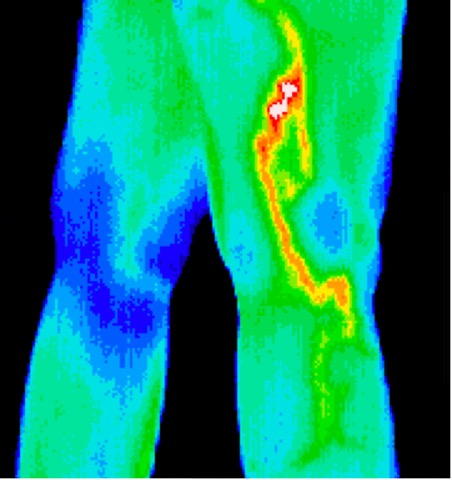

Phlebitis